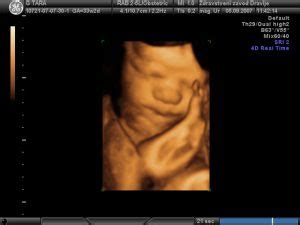

Proces nastajanja plodovnice se začne že zgodaj v nosečnosti, kmalu po oploditvi, ko se začne razvijati plodov ovoj. Sprva je njena količina skromna, le okoli 10 ml v drugem mesecu nosečnosti. V prvih tednih po oploditvi onemogoči zrast zarodka s plodnikom, kasneje pa plodu omogoča gibanje v vse smeri, ne da bi ga pri tem ovirala stena maternice. Gibanje ploda je zaradi vzgona olajšano. Hkrati blaži tudi prenos sile na plod, na primer pri udarcu v trebuh.

Drugo trimesečje (13.-27. teden): To obdobje pogosto velja za obdobje najboljšega počutja. Začetne nosečniške slabosti se umirijo, maternica s plodom pa še ni tako velika, da bi povzročala večje nelagodje. Maternica se začne povečevati in raste iz male medenice, kar lahko povzroči špikanje ali nelagodje v spodnjem delu trebuha zaradi napenjanja vezi. Ob koncu embrionalnega razvoja meri zarodek 28 mm, zaključi se obdobje zarodka in se začne obdobje ploda. Plod meri okoli 6 do 8 cm, razvijejo se mu prsti na rokah in nogah. Začnejo se spontani gibi ploda. Pod vplivom hormonov nosečnosti se upočasni prebava, pojavi se lahko zaprtje ali zgaga. Krvni tlak se lahko zniža, pojavi se lahko občutek omotice. Okoli 20. tedna se zaznajo gibi ploda. Ženske, ki so že rodile, gibe ploda običajno zaznajo prej. Plod v tem obdobju tehta okoli 300 gramov. Ob raztezanju kože na trebuhu se lahko pojavijo strije ali srbečica kože. Oko število plodovnice se povečuje, kot tudi teža ploda.

Tretje trimesečje (28.-40. teden): V tem obdobju je teža maternice že precejšnja in lahko ovira gibanje, začne se pričakovanje poroda. Maternica sega visoko nad popek in s pritiskom na želodec dodatno povzroča zgago. Velika maternica pritiska tudi navzdol v malo medenico in na mehur, zato nosečnice pogosto hodijo na vodo. Zaradi teže noseče maternice se lahko pojavijo hemoroidi. Otekati začnejo spodnje okončine, saj se količina tekočine v telesu povečuje. Pojavijo se Braxton-Hicksovi popadki, tako imenovani lažni popadki, ki so neredni, kratki in praviloma neboleči. Zaradi povečanja trebuha se spremeni težišče telesa, kar lahko povzroči bolečine v križu. Koža na trebuhu se razteza, kar lahko povzroči strije. Plod tehta okoli 1100 gramov pri 28 tednih, v 32. tednu okoli 1800 gramov, v 36. tednu okoli 2500 gramov, ob polnem terminu (40. teden) pa povprečno 3500 gramov. Maternica sega do prsnice in zaradi svoje velikosti lahko povzroča nelagodje, lahko se pojavi nespečnost. Plod se postavi v porodni kanal, ob tem se čuti blag pritisk navzdol. Pojavi se povečan izcedek iz nožnice. Znaki začetka poroda so luščenje čepa, krči, odtekanje plodovnice.